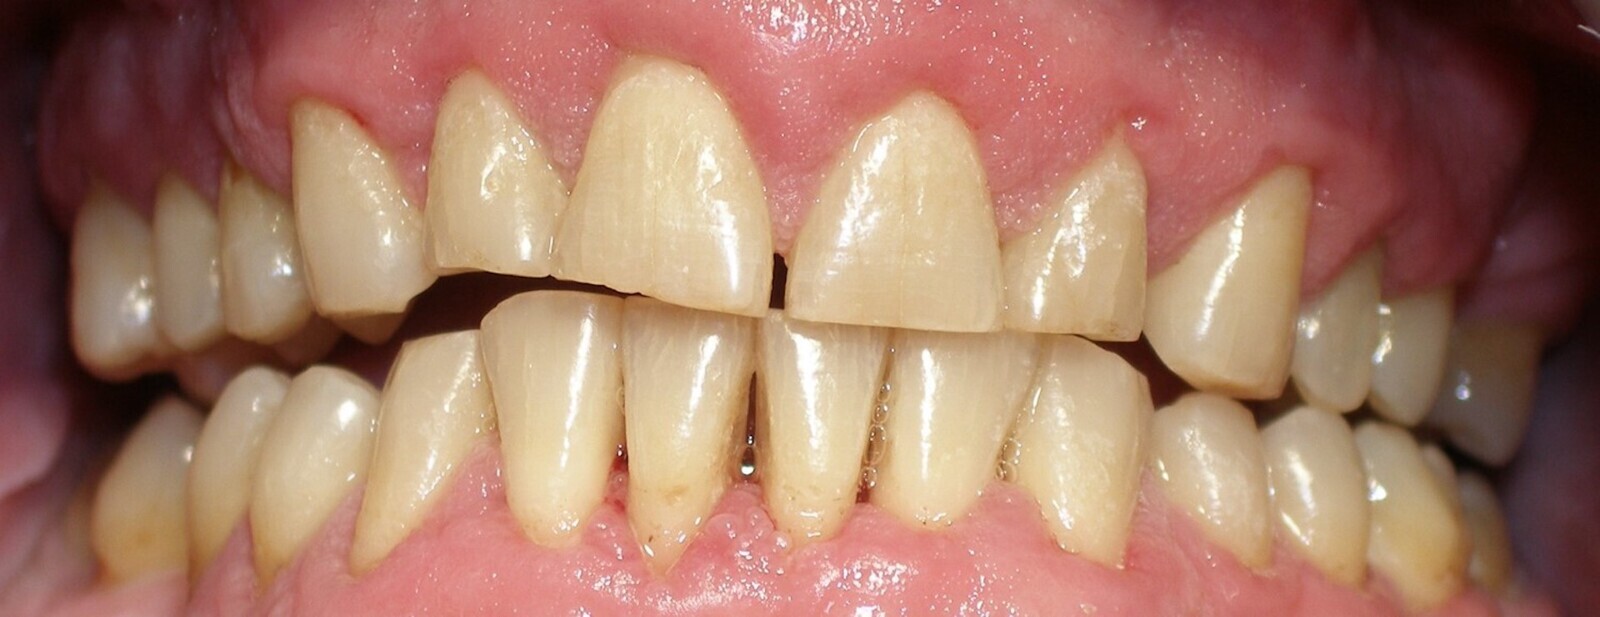

En la cirugía de tejidos blandos, la gingivectomía es probablemente uno de los tratamientos más básicos y que más frecuentemente se realizan en periodoncia quirúrgica (Figuras 17-19). Realizar una gingivectomía con láser es un procedimiento muy sencillo y a la vez bastante rápido que produce un efecto inmediato y que, comparado con una gingivectomía convencional con bisturí, ofrece una serie de ventajas como por ejemplo una hemostasia excelente, lo que mejora la visibilidad del campo y resulta en una molestia postoperatoria mínima para el paciente11.

La gingivectomía con láser es un procedimiento muy rápido y sencillo que ofrece beneficios comparado con una gingivectomía convencional (ver Figuras 17-19).

Fig. 17.

Fig. 18.

Fig. 19. Las figuras 17-19 muestran que la gingivectomía con láser es un procedimiento muy rápido y sencillo que produce un efecto inmediato y ofrece ventajas comparado con la gingivectomía convencional con bisturí.